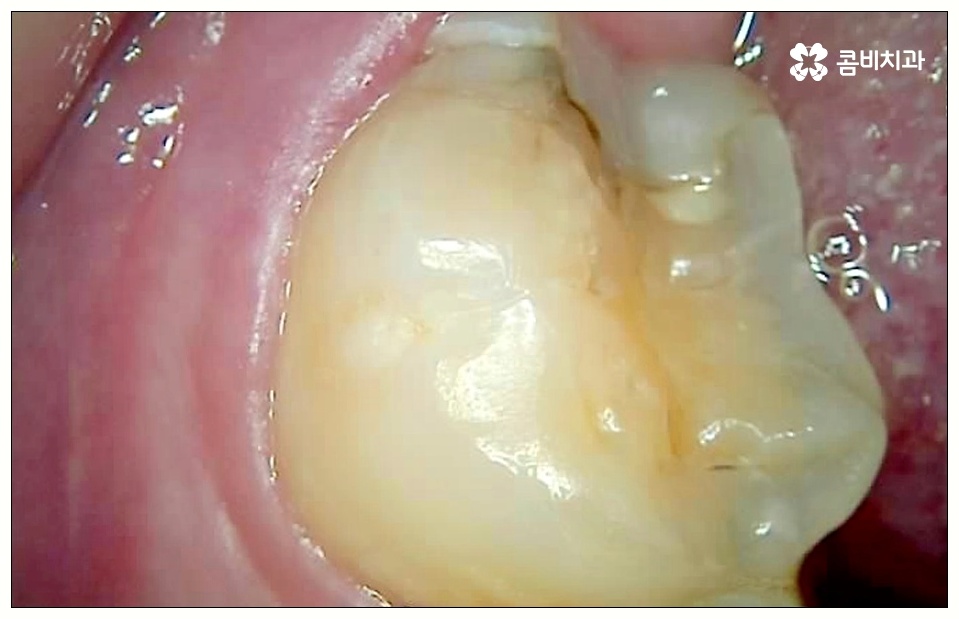

어금니는 구강 내 가장 안쪽에 자리잡고 있기 때문에 평소에도 음식물 찌꺼기가 많이 고여 있기 쉬운 치아이며 신경써서 관리해 주지 않으면 충치나 잇몸 염증이 자주 일어날 수 있는데요.

이 때 어금니 뒤쪽으로 비스듬하게 사랑니가 자리를 잡으면 부분적으로 맹출이 되면서 치아 사이에 좁은 틈새가 만들어져 여러 가지 부산물들이 끼기 쉬워지는 반면 칫솔질 등 관리는 더욱 어려워지기 때문에 구강 질환 발생률이 높아질 수 있어요.

위생 관리가 제대로 되지 않으면 치태와 치석이 늘어나 세균이 증식하면서 구취는 물론 충치가 유발되게 되는데, 이것을 방치할 경우 사랑니 자체가 썩어 옆의 어금니로 충치가 옮겨가게 되거나 사랑니와 어금니 사이 충치 발생으로 인해 어금니까지 덧씌워야 하는 상황이 올 수도 있으니 주의하실 필요가 있어요.

특히 어금니 사이 충치 는 눈에 잘 보이지 않을 뿐만 아니라 어느 정도 진행이 될 때까지 통증이 크지 않기 때문에 치료시기를 놓치게 되는 경우가 많이 있는데요.

이렇게 병증이 깊어지게 되면 치은에도 쉽게 손상이 일어나고 치아 내부 밀도가 떨어져 치아 파절이 일어날 수 있으며 결국 사랑니만 뽑는 것이 아니라 저작 기능에 중요한 역할을 하는 어금니까지 발치해야 하는 상황이 생길 수도 있기 때문에 초기에 잘 대처하실 필요가 있어요.

치아 사이 충치는 법랑질이 두꺼운 교합면, 즉 음식을 잘게 부수는 윗면이 아니라 치아와 치아 사이에 맞닿고 있어 비교적 법랑질의 두께가 얇고 신경까지의 거리가 짧은 옆면에 생기는 것이기 때문에 병증이 진행되는 속도가 빠르고 치료하기가 까다로워 될 수 있는대로 빨리 대처하실 필요가 있어요.